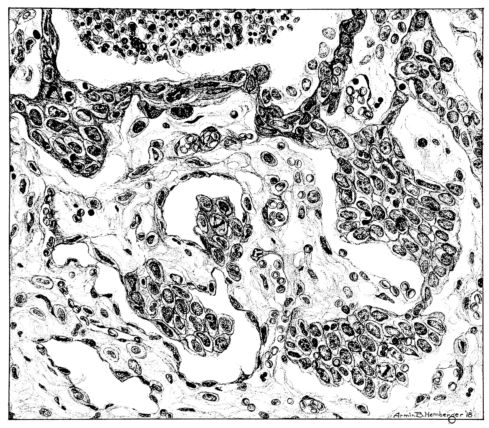

FIG. IV. AUTOPSY NO. 205. CONGESTION AND EDEMA OF THE SUBMUCOSA AND REGENERATION OF THE TRACHEAL EPITHELIUM.

The changes are less marked, perhaps, in the trachea than in its finer ramifications. The mucosa is constantly more or less destroyed and large areas, usually focal, are entirely devoid of their epithelial covering. This is replaced by a sparse exudate, composed largely of red blood cells, mucus, a small amount of fibrin, and nuclear fragments (Fig. II). It may dip into the submucosa for a short distance, but usually these indentures are associated with the ducts of the mucous glands into which the inflammatory reaction extends. A more striking feature than the exudate, however, is the edema and the congestion of the submucosa. The loose areolar tissue of the submucosa is spread widely apart, and throughout it distended blood vessels are very conspicuous. Occasionally such a vessel is broken and actual hemorrhage appears in the submucosa. Occasionally, too, the inflammation extends down the duct to the mucous gland itself, and here, also, aplastic inflammatory reaction is evident, inasmuch as the acini now stain intensely red with the cells undifferentiated from each other and specked here and there by broken remains of the dead nuclei (Fig. III). After the disease has continued for a short period, even at the end of five or six days, some regeneration of the epithelial lining may be seen (3) (Fig. IV). But despite this, the acute picture persists, and there goes on, side by side, an attempted repair characterized by epithelial regeneration and the same evidence of acute change. Since the lesion is essentially a superficial one, scars or contractures of any extent are not encountered in the trachea, even in examples of the disease that have ended fatally only after many weeks.[4]